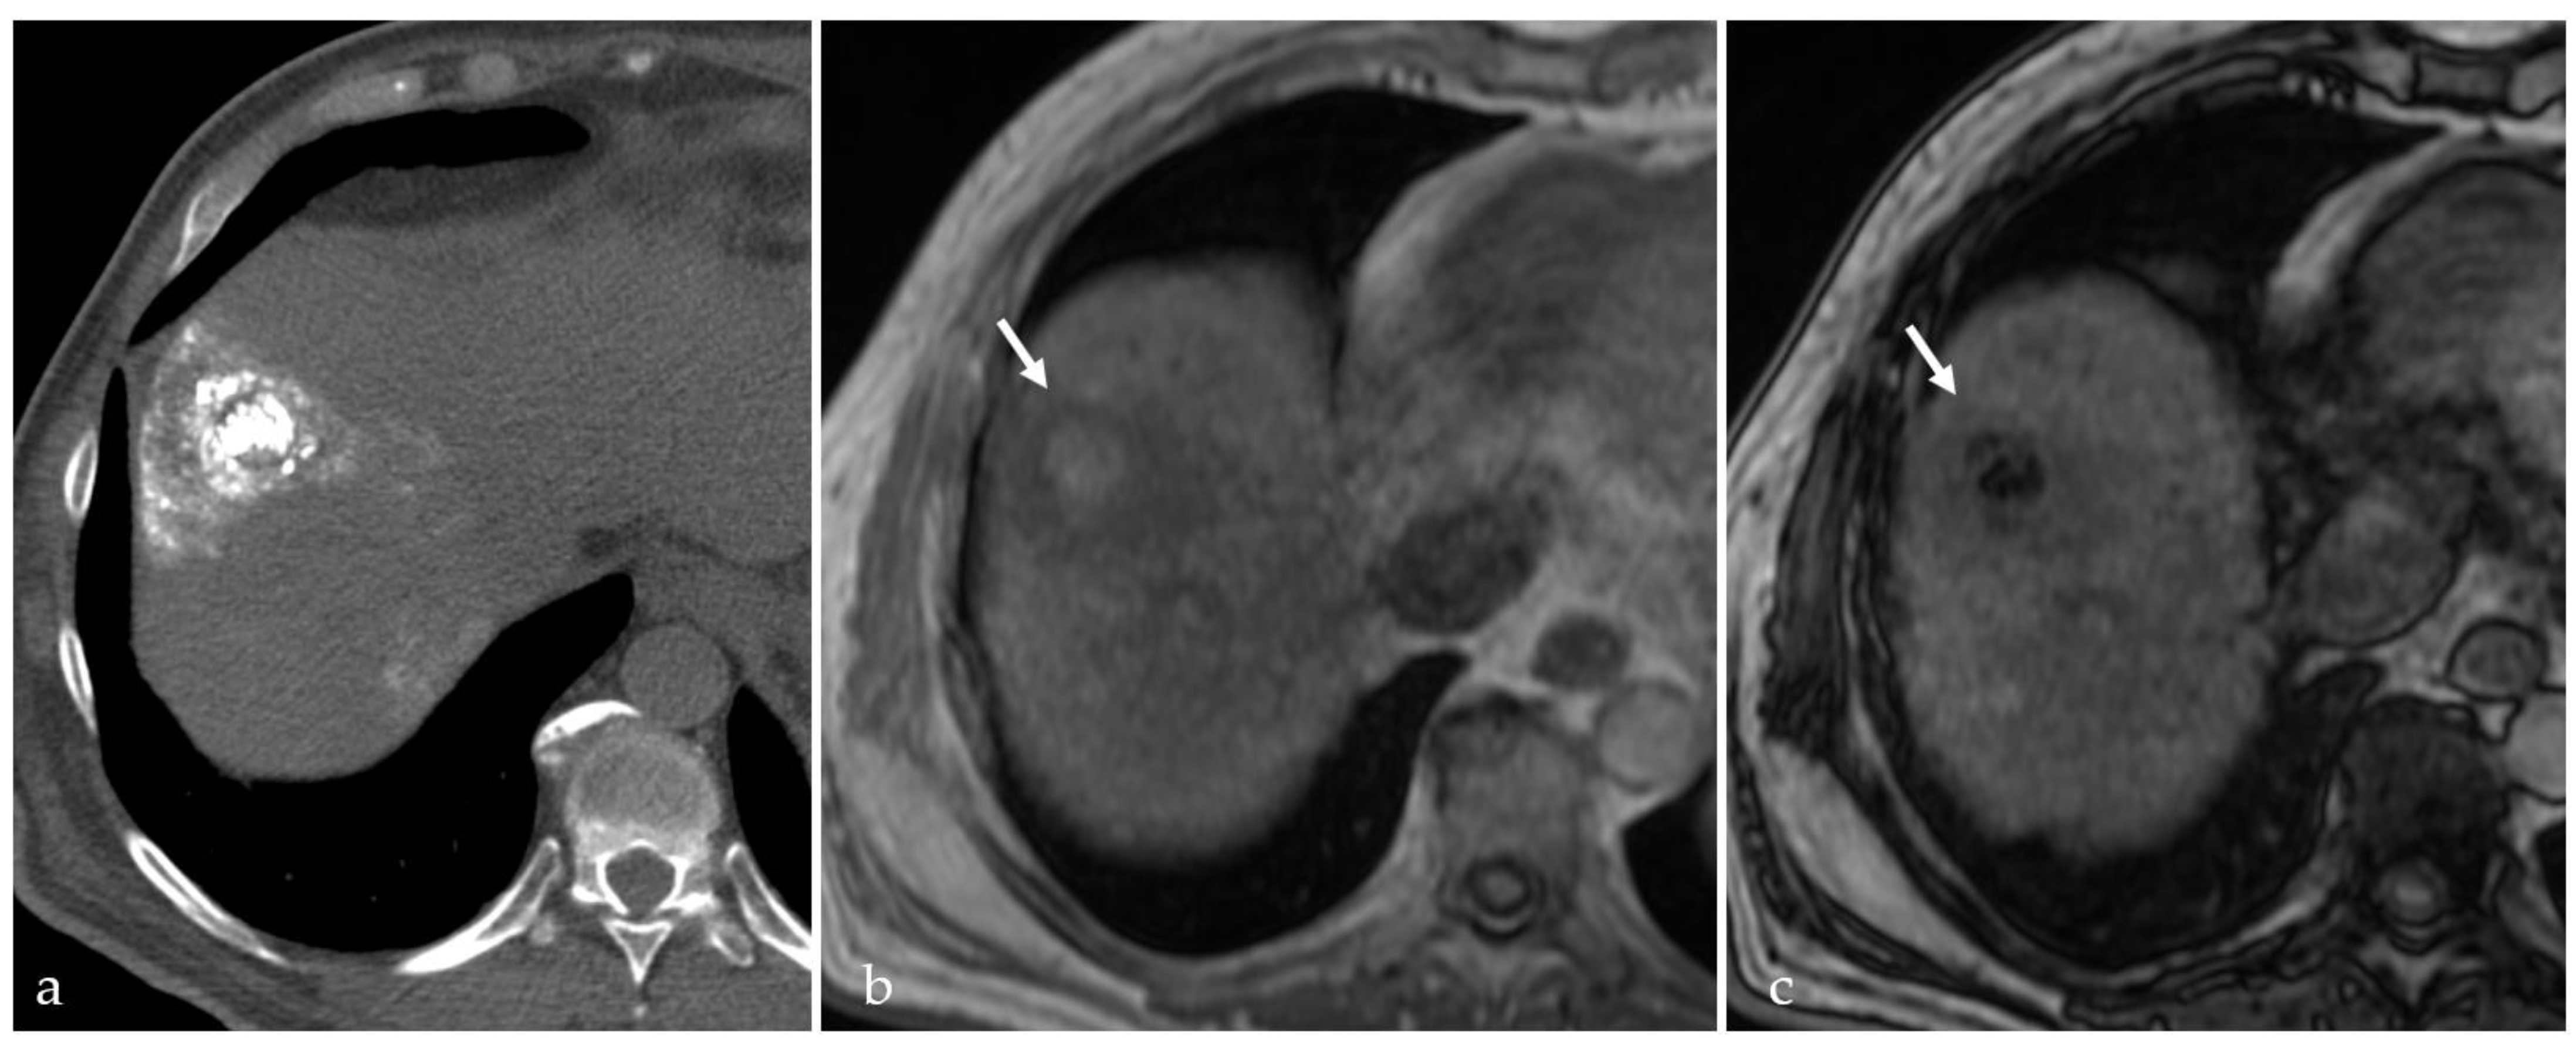

3.2. Expected Post-Treatment Imaging Features in the Absence of Viable Tumor Tissue

| RFA | 0-A | Better control for larger nodules | Not recommended for superficial or near-hilum lesions Heat sink effect | Coagulation necrosis (H-iso T1, hT2) | 40–68% |

| MWA | 0-A | Higher ablation volume Minimal heat sink effect | Ablation volume may be difficult to estimate More complications in larger nodules | Coagulation necrosis (H-iso T1, hT2) | 50–60% |